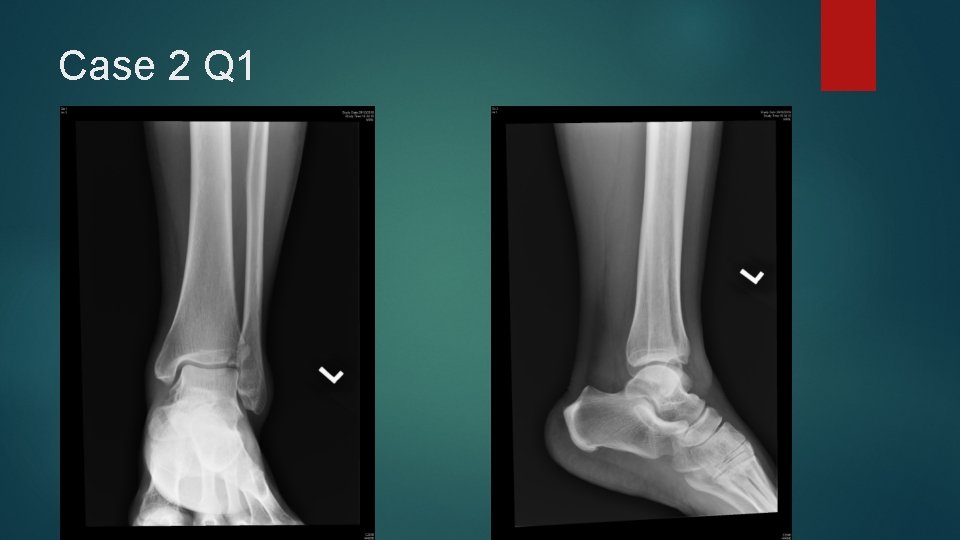

Case 2 A 42 years old lady complained of twisting injury to her left ankle after jumping from a rock about 1 meter from the ground during hiking Managed to walk immediately but called GFS later because of increasing pain No other injury complained Examination showed tenderness and swelling over the medial and anterior aspect of left ankle X-rays of her left ankle were taken

Case 2 Q 1

Case 2 Q 1 Describe the x-rays findings. (1 mark)

Case 2 Q 2 What is the significance of this fracture? (1 mark)